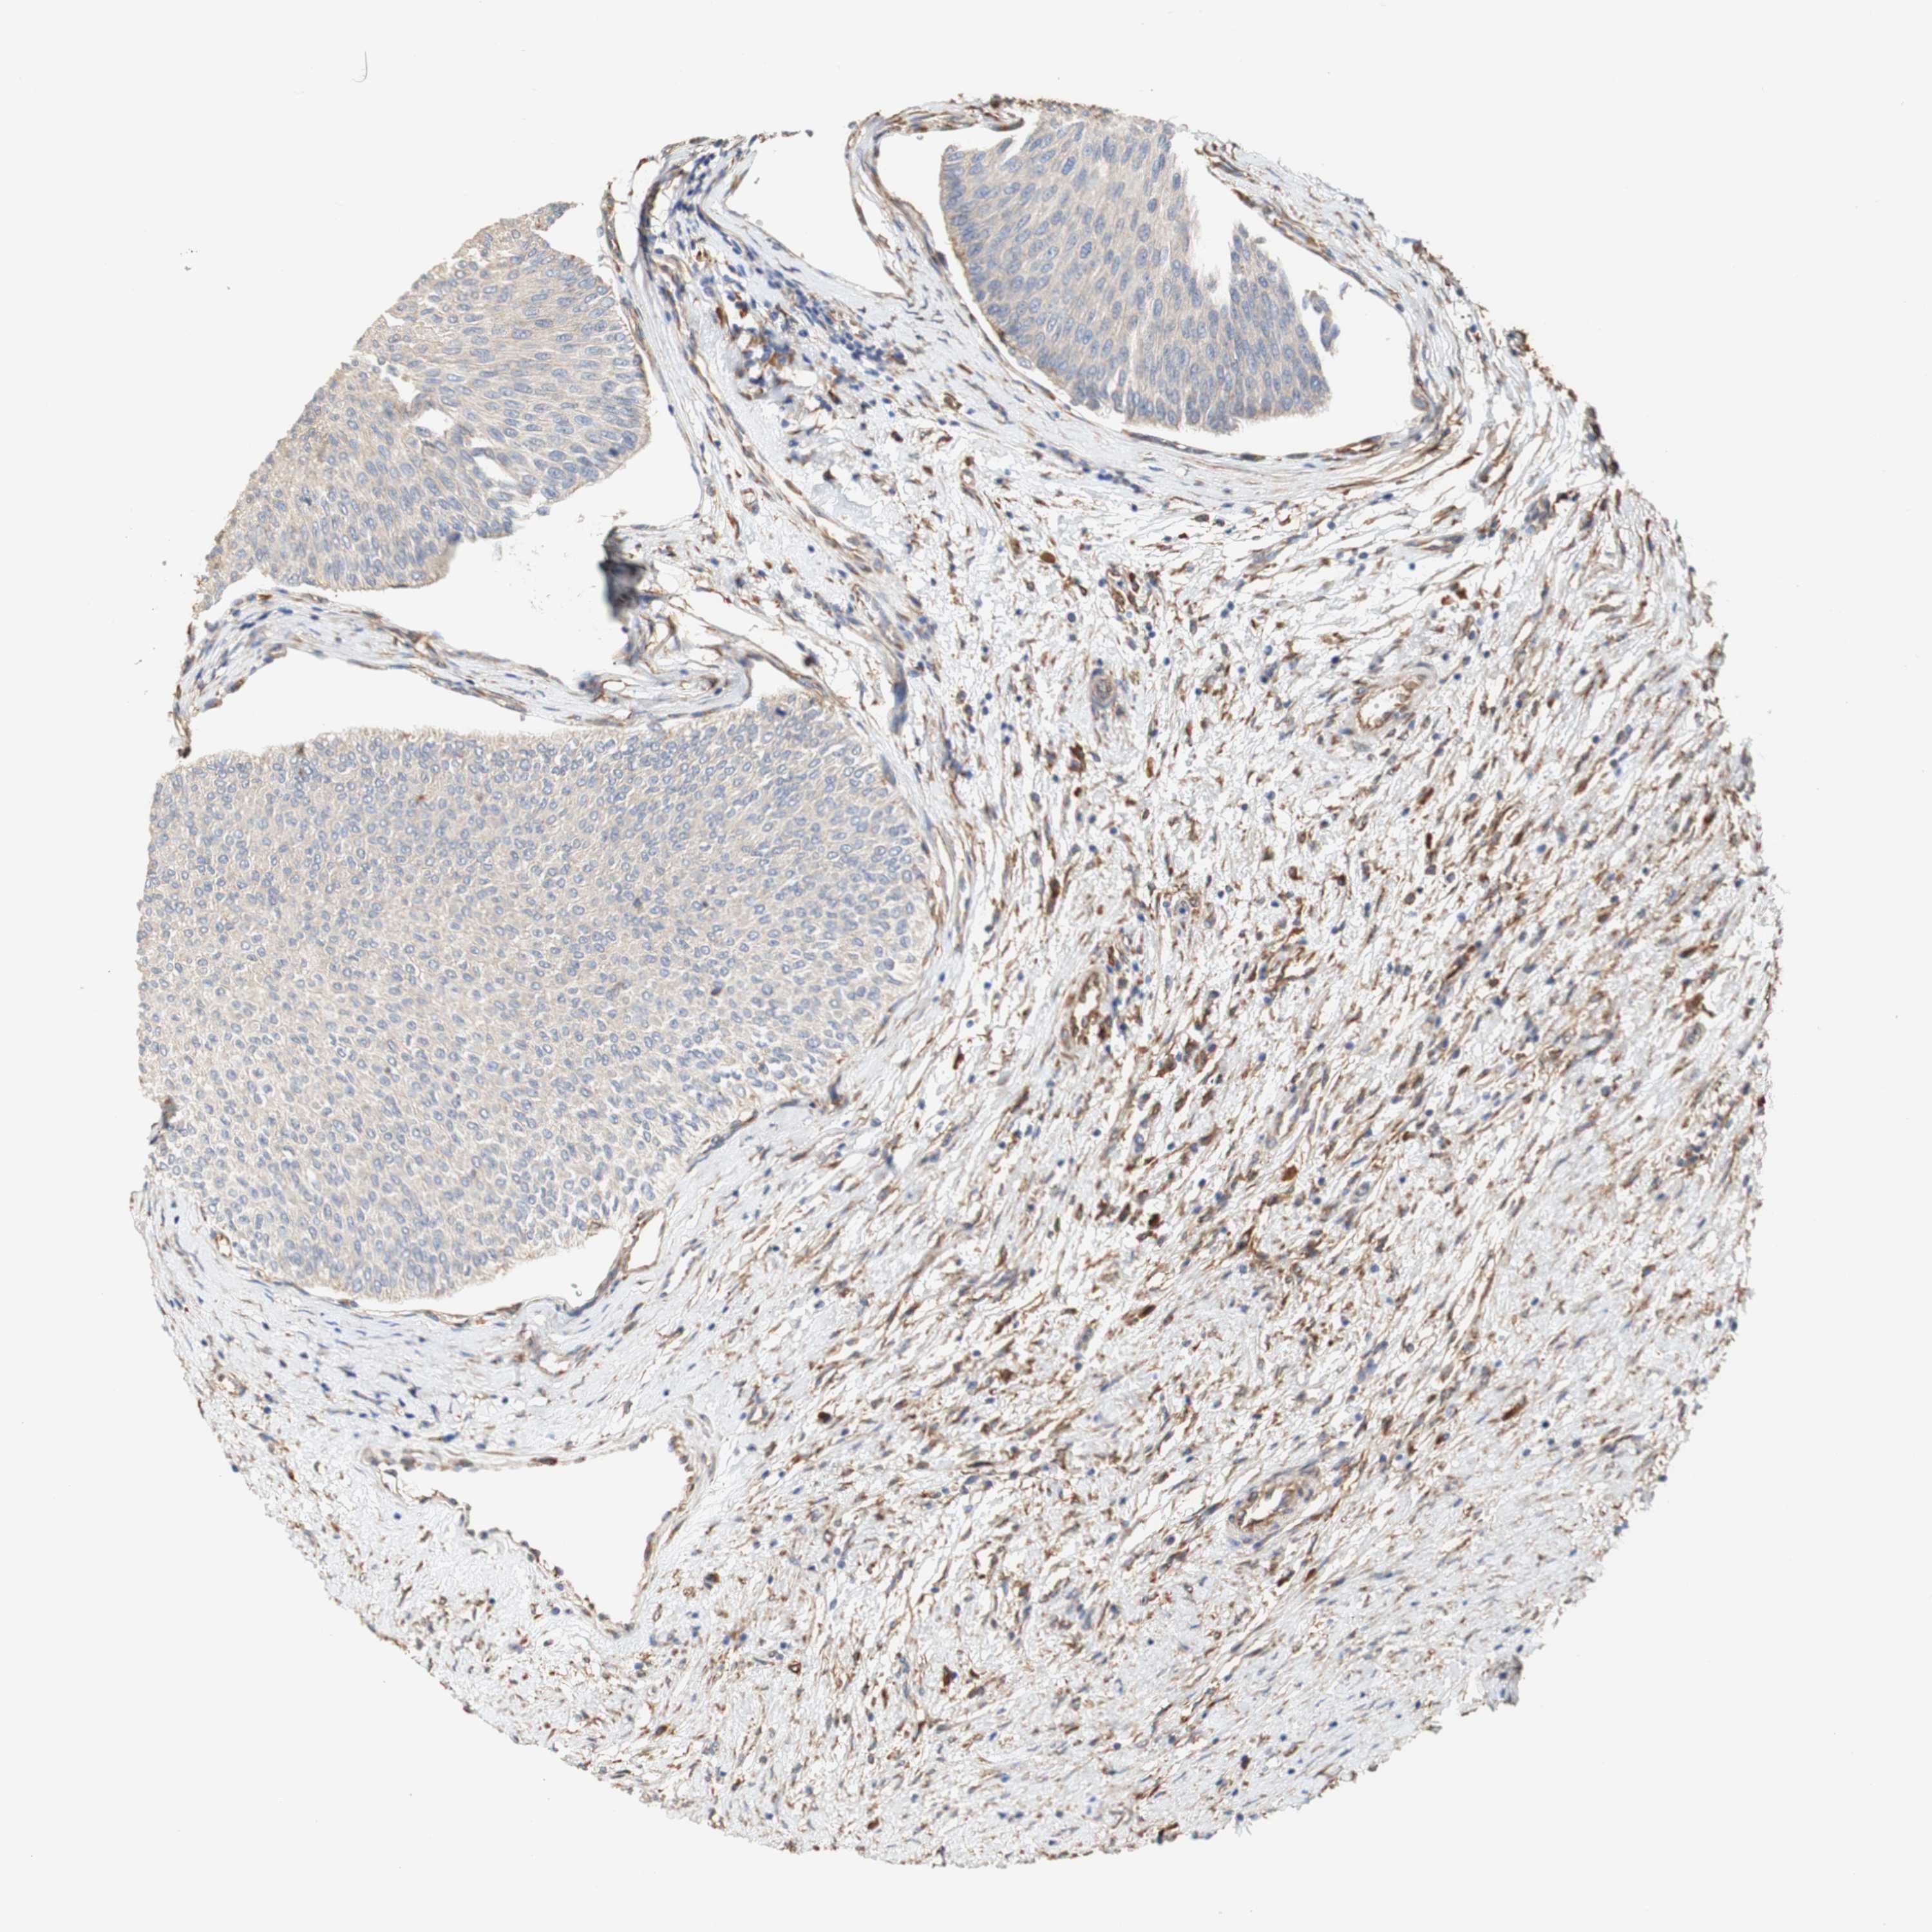

UROTHELIAL CANCER - Protein expressioni

A mouse-over function shows sample information and annotation data. Click on an image to view it in a full screen mode. Samples can be filtered based on level of antibody staining by selecting one or several of the following categories: high, medium, low and not detected. The assay and annotation is described here.

Note that samples used for immunohistochemistry by the Human Protein Atlas do not correspond to samples in the TCGA dataset.

Antibody stainingi

Antibody staining in the annotated cell types in the current human tissue is reported as not detected, low, medium, or high, based on conventional immunohistochemistry profiling in selected tissues. This score is based on the combination of the staining intensity and fraction of stained cells.

Each image is clickable and will lead to virtual microscopy that enables deeper exploration of all samples and also displays staining intensity scores, fraction scores and subcellular localization as well as patient and tissue information for each sample.

Antibody HPA011811

Staining

High

Medium

Low

Not detected

Intensity

Strong

Moderate

Weak

Negative

Quantity

>75%

75%-25%

<25%

None

Location

Nuclear

Cytoplasmic/membranous

Cytoplasmic/membranous,nuclear

Urothelial carcinoma, Low grade

Urothelial carcinoma, High grade